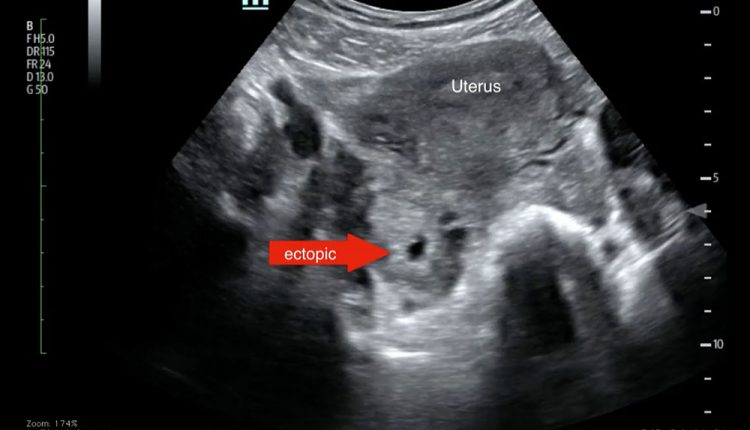

همچنین ممکن است سونوگرافی برای مشاهده وضعیت رحم و لوله های فالوپ انجام شود.

[…] ساک حاملگی در رحم دیده نشود، ممکن است که بارداری خارج از رحمی اتفاق افتاده باشد. این مساله می تواند خطرناک باشد اما […]